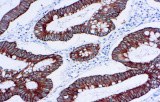

Primary antibodies for immunohistochemistry (IHC) with CE/IVD marking are essential reagents in diagnostic and research pathology, enabling the specific detection of target antigens in formalin-fixed paraffin-embedded (FFPE) tissue sections.

IHC using CE/IVD primary antibodies is a cornerstone in the characterization of gastrointestinal tumors. These antibodies assist pathologists in distinguishing epithelial from mesenchymal origins, determining tumor subtypes, and identifying primary sites in metastatic disease.

- In colorectal cancer, antibodies against cytokeratins (CK7, CK20) and transcription factors such as CDX2 facilitate accurate tumor classification and subtype differentiation.

- High specificity and sensitivity for clinically relevant antigens such as CK7, CK20, CDX2, and cadherin-17, minimizing cross-reactivity.